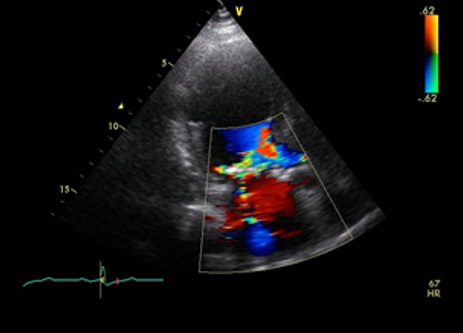

An asymptomatic 75-year-old female with past medical history of percutaneous coronary intervention for angina pectoris and chronic renal failure on hemodialysis was referred to our department for the management of left ventricular aneurysm which was pointed out on the follow-up echocardiography. Coronary angiography showed no restenosis of the stent site but 100% stenosis of distal segment of left circumflex artery which had not been detected previously. Echocardiography showed an abnormal cavity that communicated with the left ventricle through a small hole, 2cm in diameter in the lateral wall (Figure 1). Figure 2. Computed tomography scan showed an aneurysm in the lateral wall of left ventricle without pleural effusion (Figure 2). Magnetic resonance imaging showed an aneurysm with abrupt discontinuing of myocardium and narrow neck (Figure 3). Pseudoaneurysm, subepicardial aneurysm or pseudo-pseudoaneurysm was thought as differential diagnosis. Aneurysmectomy and patch closure was planned. Surgery was performed via medial sternotomy. Cardiopulmonary bypass (CPB) was carried out with cannulation of the aorta and the right atrium under cardiac arrest and mild hypothermia. Macroscopically, a subepicardial little red aneurysmal site with a weakened wall was seen at the apical part of the left ventricle. Sign of rupture, adhesion to the surrounding structures or pericardial effusion was not seen. The aneurysmal sac was opened and a sclerotic wall was seen. There was a narrow neck at the base of the incised aneurismal sac communicating with the left ventricular cavity. Myocardium was not contained in the aneurysm cavity (Figure 4). Following the resection of the aneurysm, the defect was patch closed with Gelweave graft.  Two Teflon pledgets were used to reinforce the ventricle suture on the outside. The weaning from CPB and postoperative course were uneventful.

Figure 1. Transthoracic echocardiography showed abrupt myocardial interruption in the inferior wall. The aneurysm was 16mm×20mm in size without external expansion.